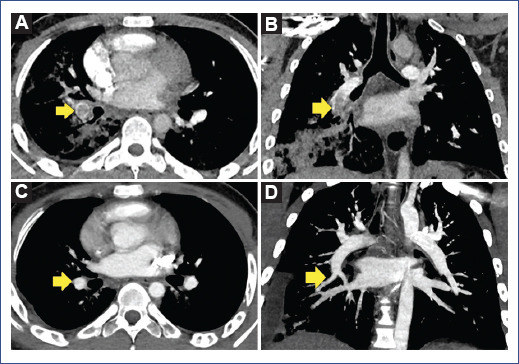

The patient initially had a favorable evolution. The fever resolved 36 h after admission, and there was a progressive decrease in oxygen requirement (1.5 L/min). Laboratory tests on day 3 of hospitalization showed a marked decrease in acute-phase reactants (Table 1). On day 7 of hospitalization, the patient referred chest pain at the right lower costal level, fever, and hemoptysis (± 100 cc) on two occasions associated with respiratory distress and oxygen requirement (2 L/min). Blood pressure was normal. Control tests showed leukocytosis with neutrophilia, mild lymphopenia, and increased C-reactive protein (CRP), ferritin, LDH, creatine kinase, and fibrinogen, and a marked increase in D-dimer (50-fold its baseline value) (Table 1). Based on respiratory deterioration, hemoptysis, elevated D-dimer, and acute phase reactants, PE was suspected. Pulmonary angiography showed a ground glass infiltrate in the right lung field and left lower lobe, extensive consolidation in the right lower lobe, and extensive thrombus in the right inferior lobar artery of 2.5 × 1.2 cm extending into the posterior branch. These results were consistent with the diagnosis of PE plus pneumonia reported in COVID-19 CO-RADS 5 (COVID-19 data and reporting system) (Figure 2). In addition, an electrocardiogram was performed to assess cardiac involvement, which showed a right bundle branch block and left anterior hemiblock; however, the echocardiogram did not show any alterations, and there was no clinical evidence of cardiac compromise. Anticoagulant treatment was initiated using low-molecular-weight heparin (enoxaparin 40 mg) subcutaneously every 12 h, followed by antibiotic coverage and systemic corticosteroid. In addition, immunological studies were also performed: anticardiolipin antibodies, anti-B2 glycoprotein, antinuclear antibodies, anti-neutrophil cytoplasm antibodies, and anti-DNA antibodies with negative results, however, lupus anticoagulant was positive.

Figure 2 A and B: angiotomography showing an extensive acute thrombus in the right inferior lobar artery with extension to the apical and posterior branches associated with extensive consolidation in the right lower lobe. C and D: after treatment, the resolution of the thrombus and right pleural effusion associated with ipsilateral pulmonary basal consolidation was observed.

During his evolution, the patient did not present hemodynamic compromise and did not require ICU admission or mechanical ventilation. Therefore, supplemental oxygen was withdrawn on day 10 of hospitalization. On day 15, we switched from enoxaparin to oral anticoagulation with rivaroxaban 15 mg orally every 12 h for the first 3 weeks and then 20 mg every 24 h continuously for 3 months. Control CT pulmonary angiogram 1 month after diagnosis showed complete thrombus resolution. The patient's clinical, laboratory, and radiological evolution was favorable. At present, he continues to be monitored by the hematology, cardiology, and pneumology departments.